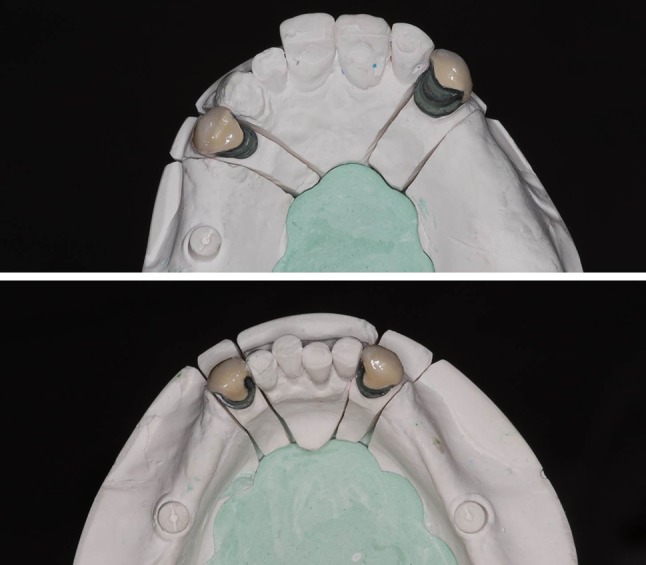

After the periodontal therapy, with the patient in appropriate oral condition, the rehabilitation using a RPD was began. Initially, pillars (# 5, 11, 22 and 27) received metal-ceramic milled crowns, which acted as guides to attach the prosthesis, and improve the teeth design and retention of the clasps (Fig. 3a, b). Crowns were placed in position and were removed using condensation silicone impression (Speedx, Vigodent/Coltene, Rio de Janeiro, Brazil). A cast model was obtained to facilitate the fabrication of the cobalt-chromium alloy framework of the RPD. The framework was developed maintaining a space around the healing caps, allowing O-ring capture (Fig. 4a, b). A wax plan of the metal framework was then made, for mounting to the teeth, which permitted an esthetic and functional trial (Figs. 5, 6).

Fig. 3.

Metal-ceramic milled crowns in the master cast